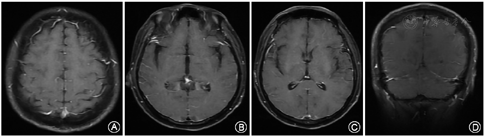

2020年11月25日患者劳累后出现睡眠障碍,伴有轻度头痛。11月26日起患者无明显诱因出现发热,体温38.5 ℃,自行服用连花清瘟胶囊效果不理想。11月27日早晨体温升至39.3 ℃,口服布洛芬胶囊后体温可下降,但仍有间断发热,故就诊于当地医院,完善腰穿脑脊液压力300 mmH2O,蛋白0.5 g/L,糖和氯化物正常,细胞数28×106/L(单核比例89.8%),具体腰穿检查结果见表1。予以脱水、抗感染和抗病毒治疗后,患者仍有发热伴头痛,故于12月3日转入我院,入住急诊科。病程中否认意识不清、四肢抽搐、精神异常、口干、眼干、关节痛、脱发、口腔溃疡、异常皮疹等症状。入院体检:体温37.1 ℃,脉搏73次/min,呼吸22次/min,血压139/90 mmHg(1 mmHg=0.133 kPa),双肺呼吸音粗,左肺可闻及湿性啰音,心率73次/min,律齐,未闻及杂音。腹软,无压痛及反跳痛,肝脾未触及,肾区无叩痛,双下肢无水肿。专科体格检查:神志清楚,精神差,情绪淡漠,反应迟钝,言语缓慢清晰。颈抵抗,颌下三横指,克氏征阴性,布氏征可疑阳性。双侧额纹对称,双眼活动度可,未见眼震。双瞳等大等圆,对光反射灵敏。双侧鼻唇沟对称,嘴角无明显歪斜,伸舌居中。四肢肌张力可,肌力Ⅴ级。感觉系统未见明显异常,双侧共济运动稳准,双侧腱反射对称,双侧病理征未引出。辅助检查:血常规、肝肾功、血清离子、凝血功能及传染病未见明显异常。增强头颅核磁可见双侧软脑膜略有增强(图1)。急诊科考虑为"颅内感染",予以阿昔洛韦0.25 g 1次/12 h抗病毒治疗、左氧氟沙星0.5 g 1次/d及甘露醇125 ml 1次/8 h脱水治疗。

12月4日患者转入神经内科监护室,再次复查腰穿脑脊液压力260 mmH2O,蛋白1.29 g/L,糖和氯化物正常,细胞数50×106/L(单核比例98%),具体腰穿检查结果见表1,细胞学检查提示淋巴细胞反应,送检中枢神经系统感染病原微生物高通量基因检测、自身免疫性脑炎、MOG抗体、副肿瘤综合征抗体、寡克隆带、抗酸杆菌涂片、阿利新蓝染色均为阴性。血清病毒学中EB病毒衣壳抗原IgM(62 U/ml)、单纯疱疹病毒Ⅰ型IgG、巨细胞病毒IgG、EB病毒衣壳抗原IgG和肺炎衣原体IgG均为阳性,脑脊液病毒学抗体均为阴性。完善头颅静脉窦核磁成像未见明显异常,红细胞沉降率70 mm/h,肿瘤标志物、甲功、糖化血红蛋白等均未见明显异常,风湿免疫性抗体中可见ANA阳性,滴度1∶100,颗粒+浆粒型,抗dsDNA IgG型25.9(<20)U/ml,抗SSA IgG型(+),抗Ro-52 IgG型(++),抗线粒体抗体2型IgG型(+++),抗M2-3E(BPO)IgG型(+++)。经风湿免疫科建议后行腮腺同位素造影提示双侧腮腺及双侧颌下腺功能正常,唇腺活体组织检查提示间质内见3处淋巴细胞浸润灶,其中1灶淋巴细胞数目大于50个/灶(图2)。眼干三项滤纸试验右眼9 mm,左眼4 mm,角膜荧光染色双侧阳性,泪膜破裂时间右侧5 s,左侧4 s。诊断考虑干燥综合征相关的脑膜脑炎,治疗于2020年12月22日开始给予甲泼尼龙48 mg/d,白芍总苷胶囊0.6 g/次,2次/d,硫酸羟基氯喹200 mg/次,1次/d。患者治疗的第4天,患者头痛发热症状明显好转。2021年1月4日复查腰穿压力180 mmH2O,细胞数下降至14×106/L。2021年1月6日出院,出院后患者继续口服甲泼尼龙48 mg/d,计划每2周减半量,其余药物剂量同前。2021年4月随访患者未再出现发热及头痛症状,已恢复正常生活,复查红细胞沉降率9 mm/h,ANA阴性,滴度<1∶10,抗dsDNA IgG型、抗SSA IgG型、抗Ro-52 IgG型、抗线粒体抗体2型IgG型和抗M2-3E(BPO)IgG型均已转为阴性。